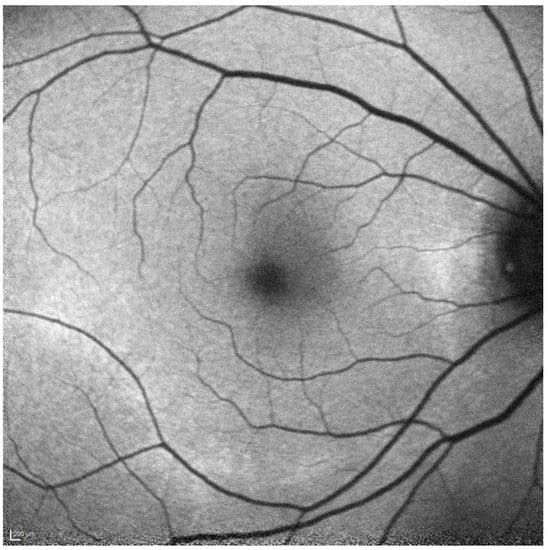

- Ahn, S.J.; Lee, S.U.; Lee, S.H.; Lee, B.R. Evaluation of Retromode Imaging for Use in Hydroxychloroquine Retinopathy. Am. J. Ophthalmol. 2018, 196, 44–52. [Google Scholar] [CrossRef] [PubMed]

- Acton, J.H.; Cubbidge, R.P.; King, H.; Galsworthy, P.; Gibson, J.M. Drusen Detection in Retro-Mode Imaging by a Scanning Laser Ophthalmoscope. Acta Ophthalmol. 2011, 89, e404–e411. [Google Scholar] [CrossRef] [PubMed]

- Giansanti, F.; Mercuri, S.; Serino, F.; Caporossi, T.; Savastano, A.; Rizzo, C.; Faraldi, F.; Rizzo, S.; Bacherini, D. Scanning Laser Ophthalmoscopy Retromode Imaging Compared to Fundus Autofluorescence in Detecting Outer Retinal Features in Central Serous Chorioretinopathy. Diagnostics 2022, 12, 2638. [Google Scholar] [CrossRef]